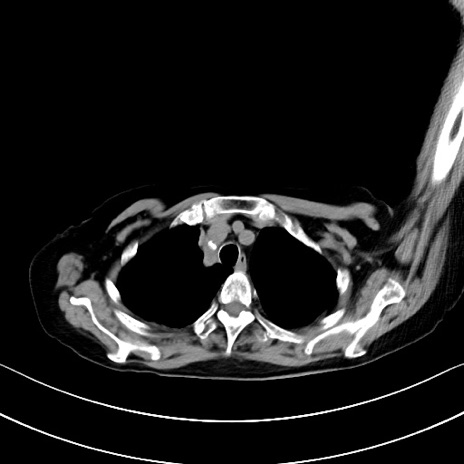

症例40(横断像)他院1日前

横断像

他院CT